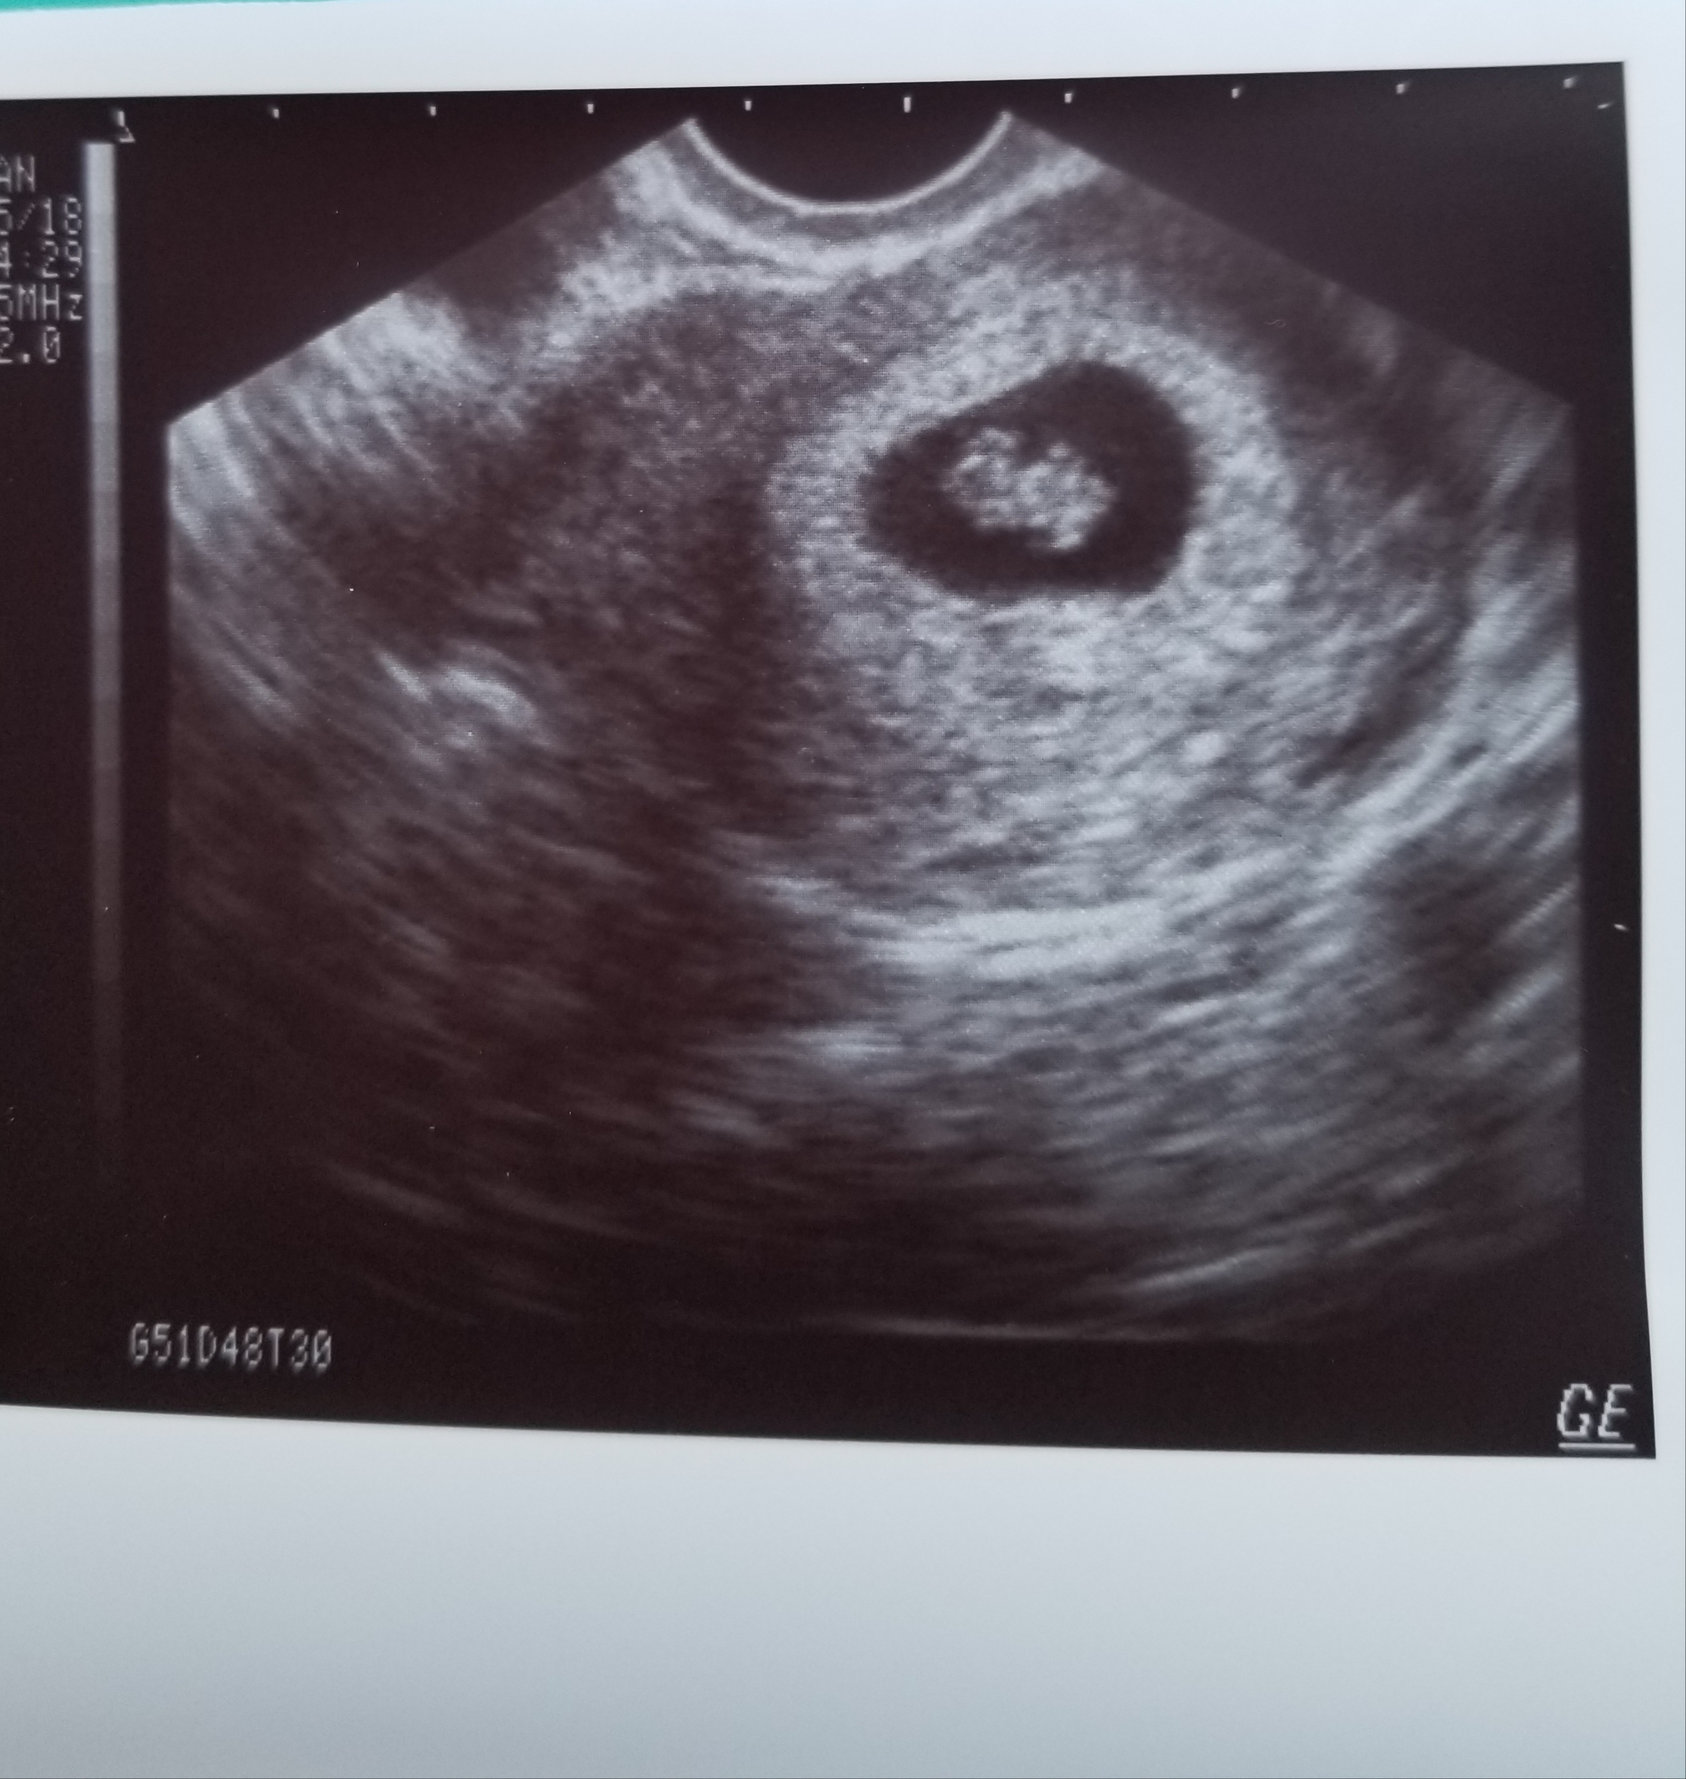

This was at 7w3d, transvaginal US. Doctor did it in his office with his little old school machine, that's why it's so grainy lol! Saw heartbeat and baby wiggling! Due 7/21, this is my second pregnancy, first one ended in ectopic with rupture last June